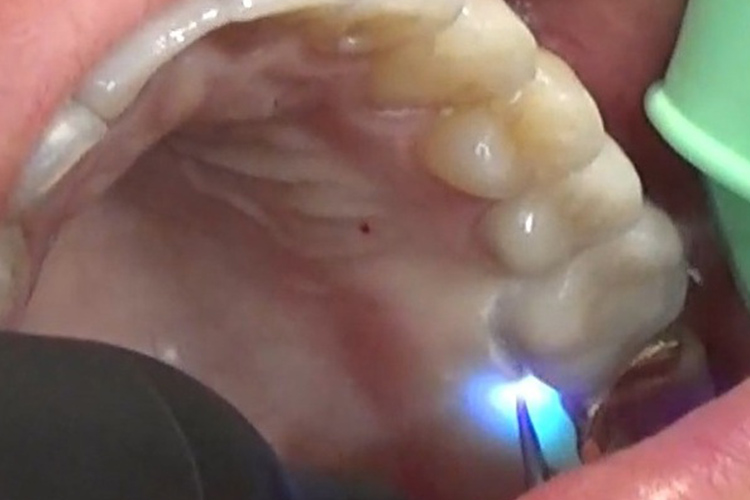

深い歯周ポケットに青いレーザー光と過酸化水素水を照射し、患部を殺菌します。

※照射前と部位が異なりますが、照射直後は、歯茎が白くなります。これは、高い殺菌力が発揮され菌が死滅したことにより生じています。数日~1週間程度で消えます。

深い歯周ポケットに青いレーザー光と過酸化水素水を照射し、患部を殺菌しています。